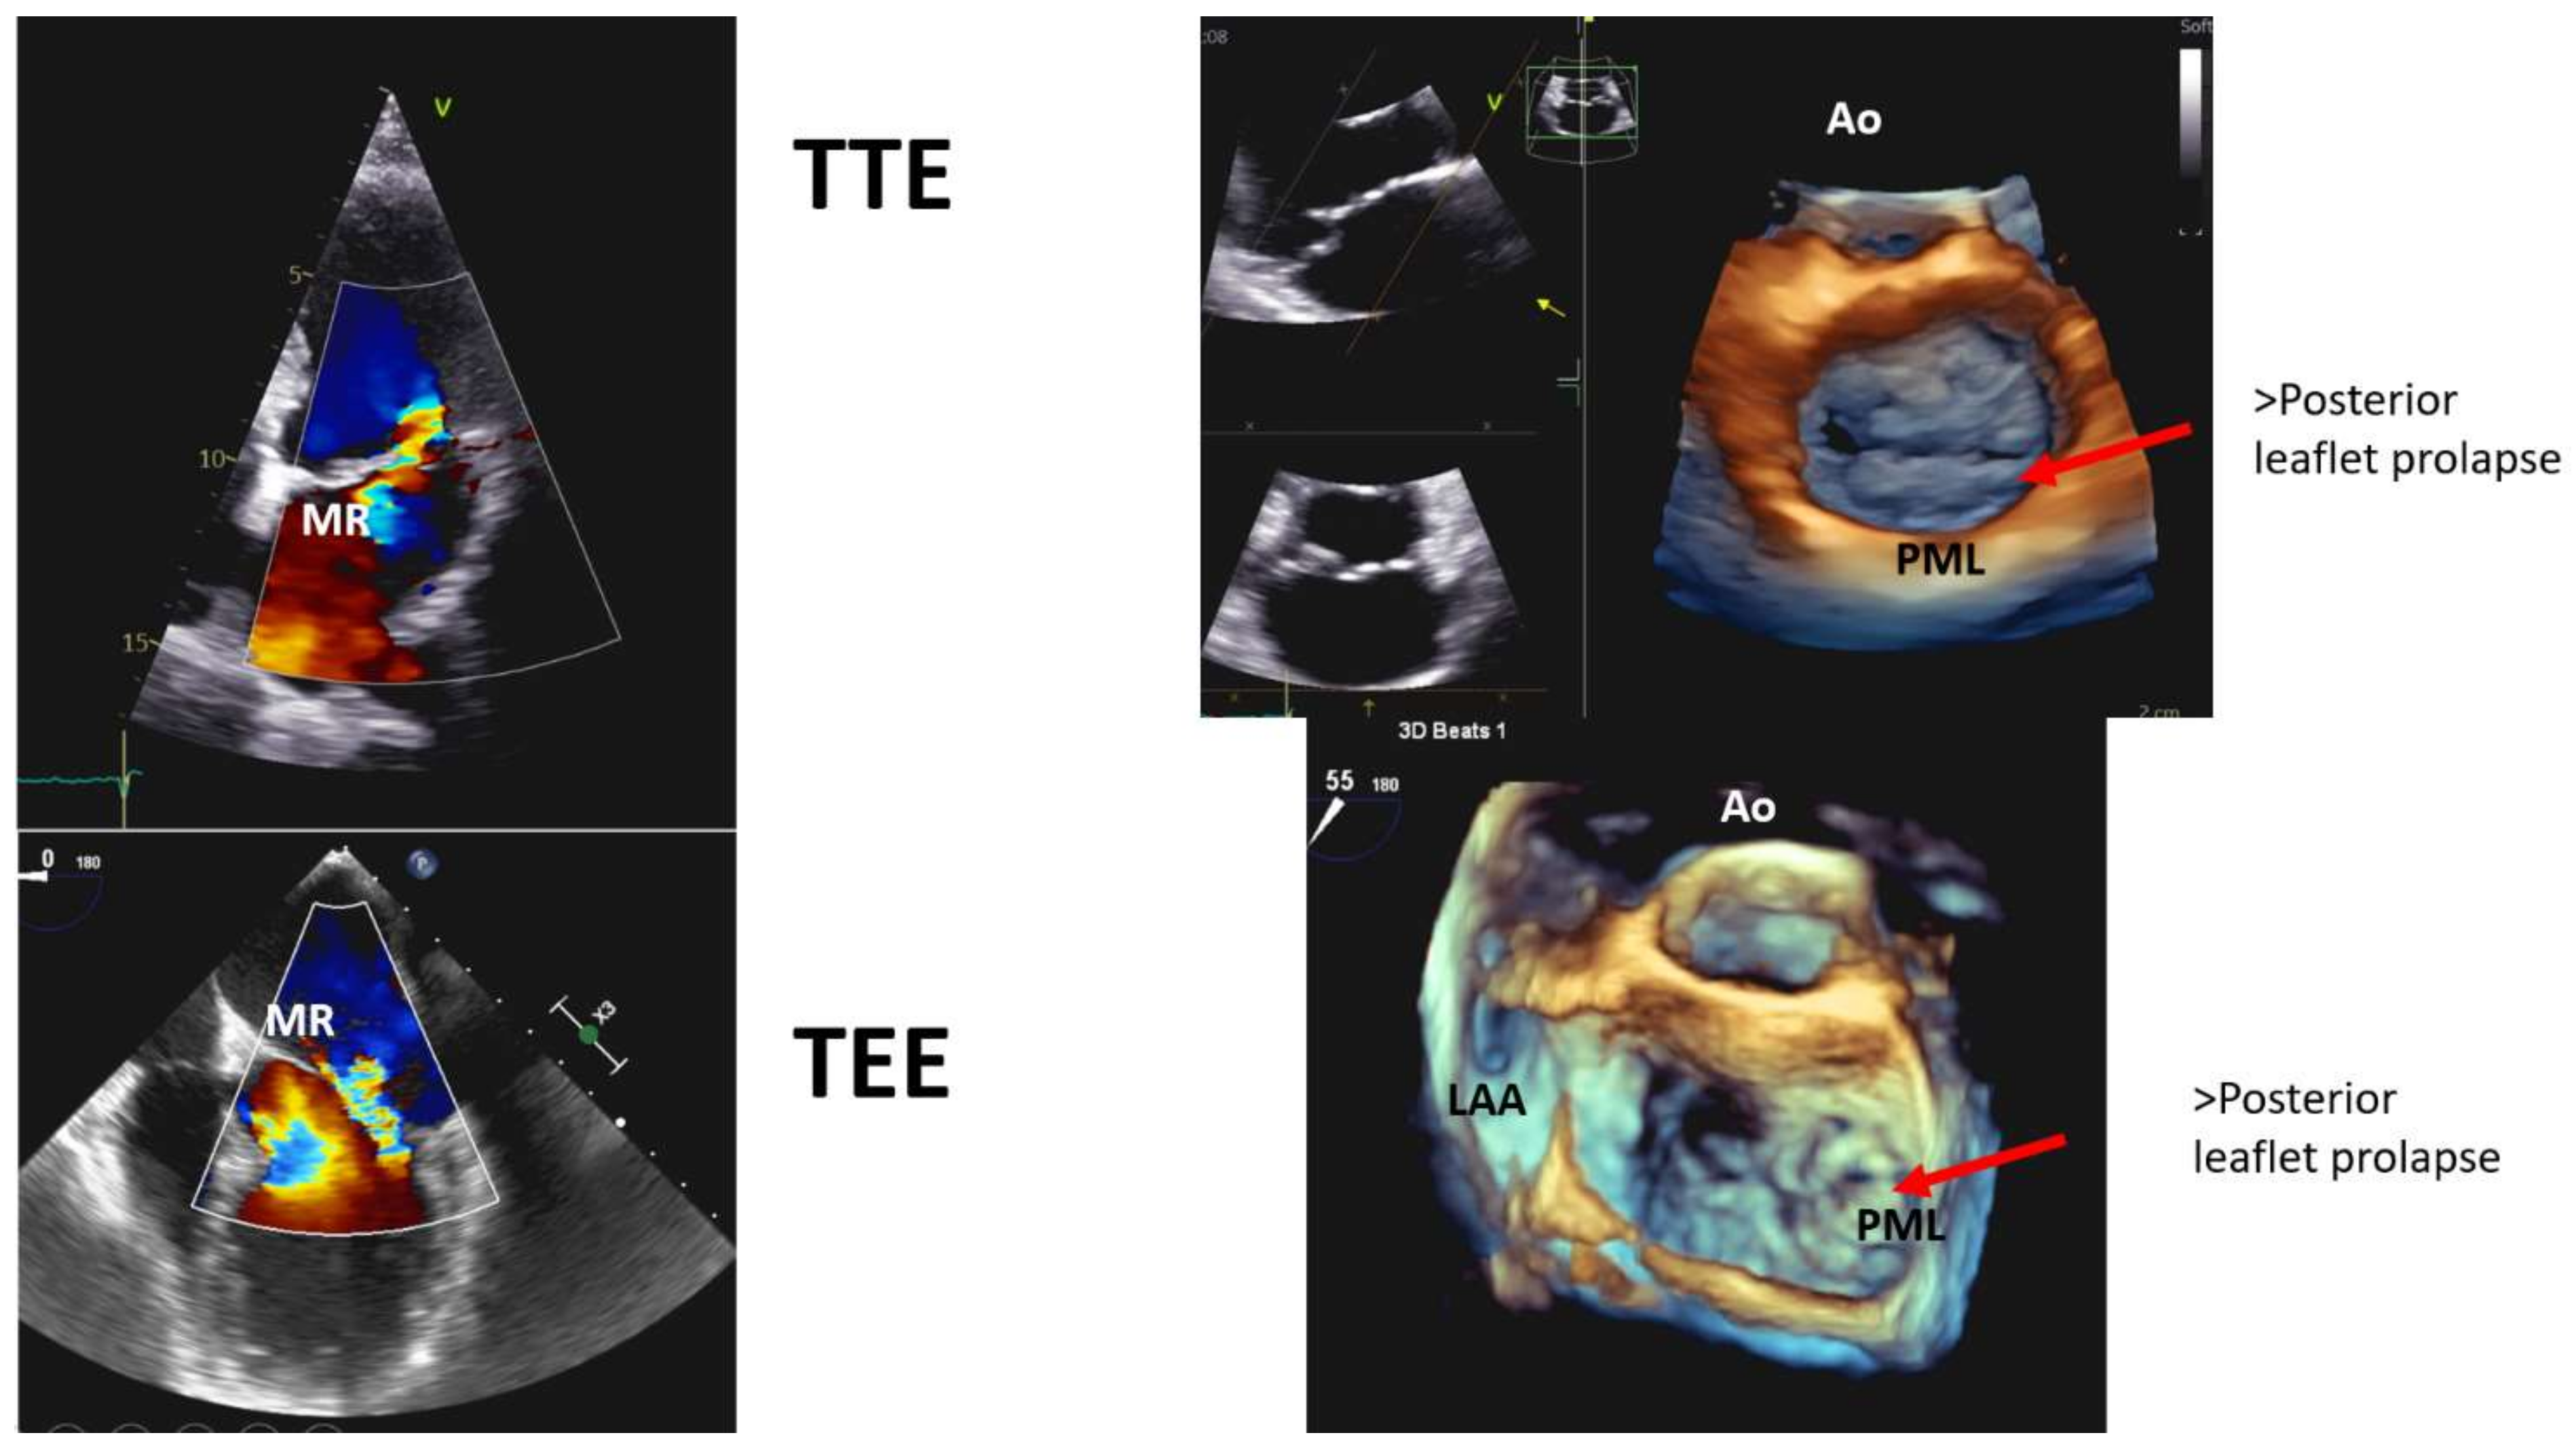

| TTE findings | Bileaflet prolapse |

| Myxomatous degeneration | |

| Moderate to severe MR (only in 36% of cases) | |

| Mitral annulus disjunction | |

| TEE | Additional information on MR severity |

| Detailed mitral valve anatomy | |